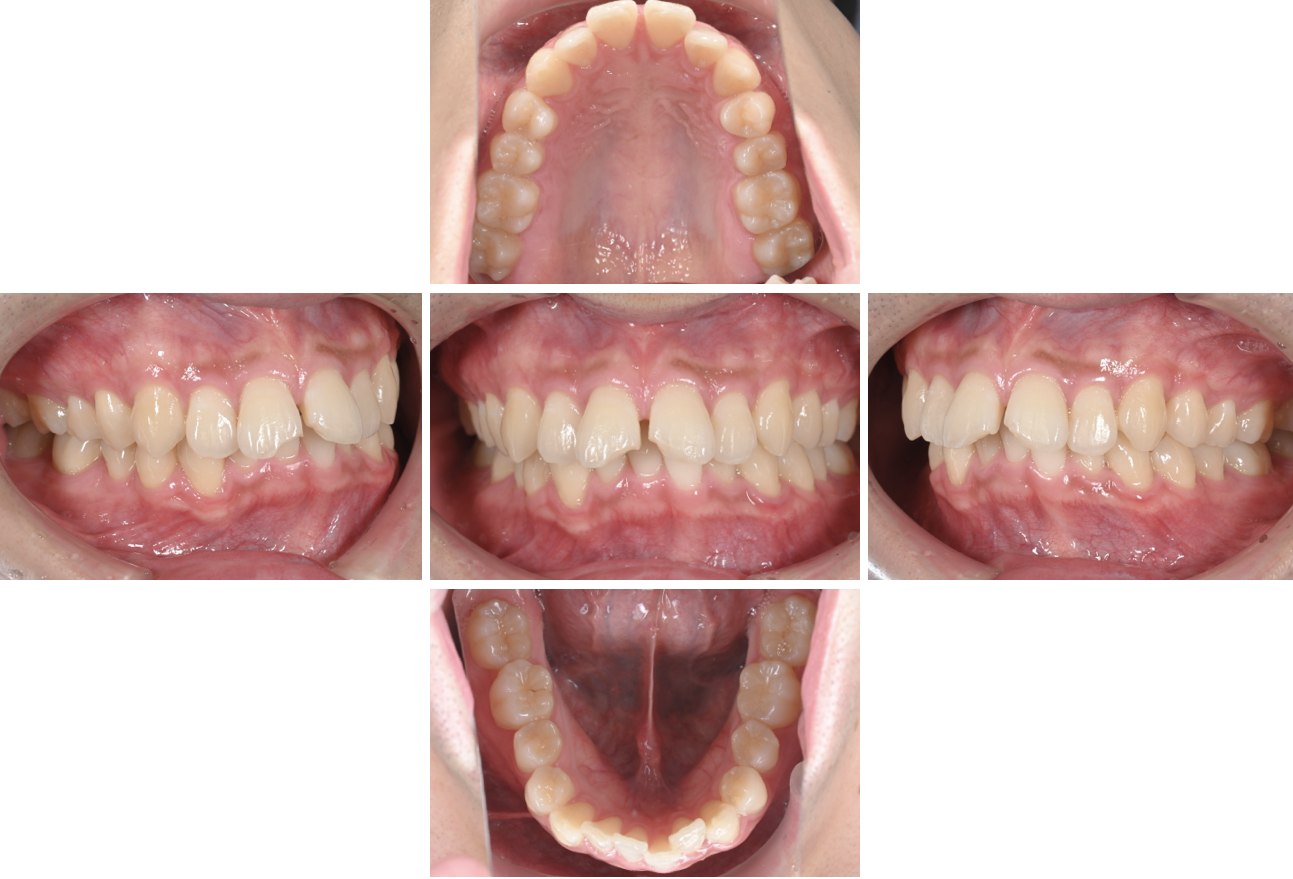

《治療の経過①》

《マウスピース矯正中》

マウスピース矯正の治療途中です。

透明で、目立ちにくいのが特徴です。